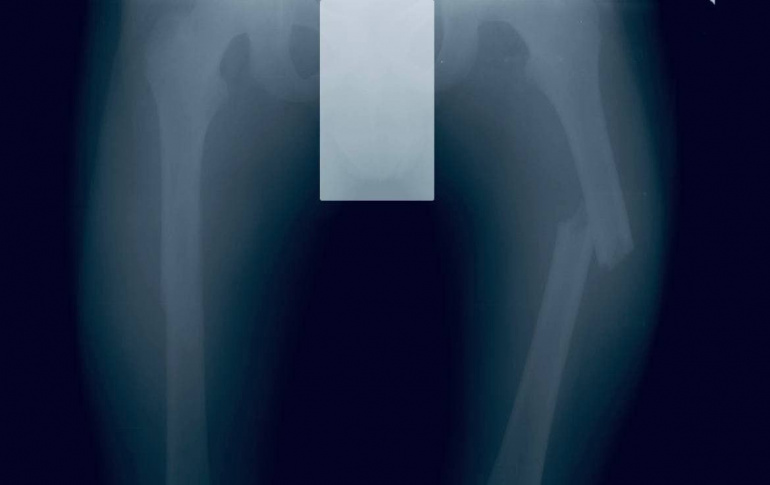

В Подмосковье 10-летний ребёнок сломал оба бедра, катаясь с горки «паровозиком»

В Московскую областную детскую клиническую травматолого-ортопедическую больницу 10-летний Ваня (имя изменено) поступил с болями в области бёдер. Оказалось, что бёдра мальчик сломал во время катания с горки «паровозиком». Подробности рассказал главврач МОДКТОБ Александр Григорьев.

— Отломки костей сопоставили и зафиксировали титановыми эластичными стержнями, — сообщил Александр Григорьев. — Когда пациент полностью восстановится, его ждёт повторная операция для удаления металлических конструкций.

Сейчас Ваня чувствует себя хорошо, его уже выписали на амбулаторное лечение.

Фото: Айдар Насыров, пресс-служба правительства Московской области